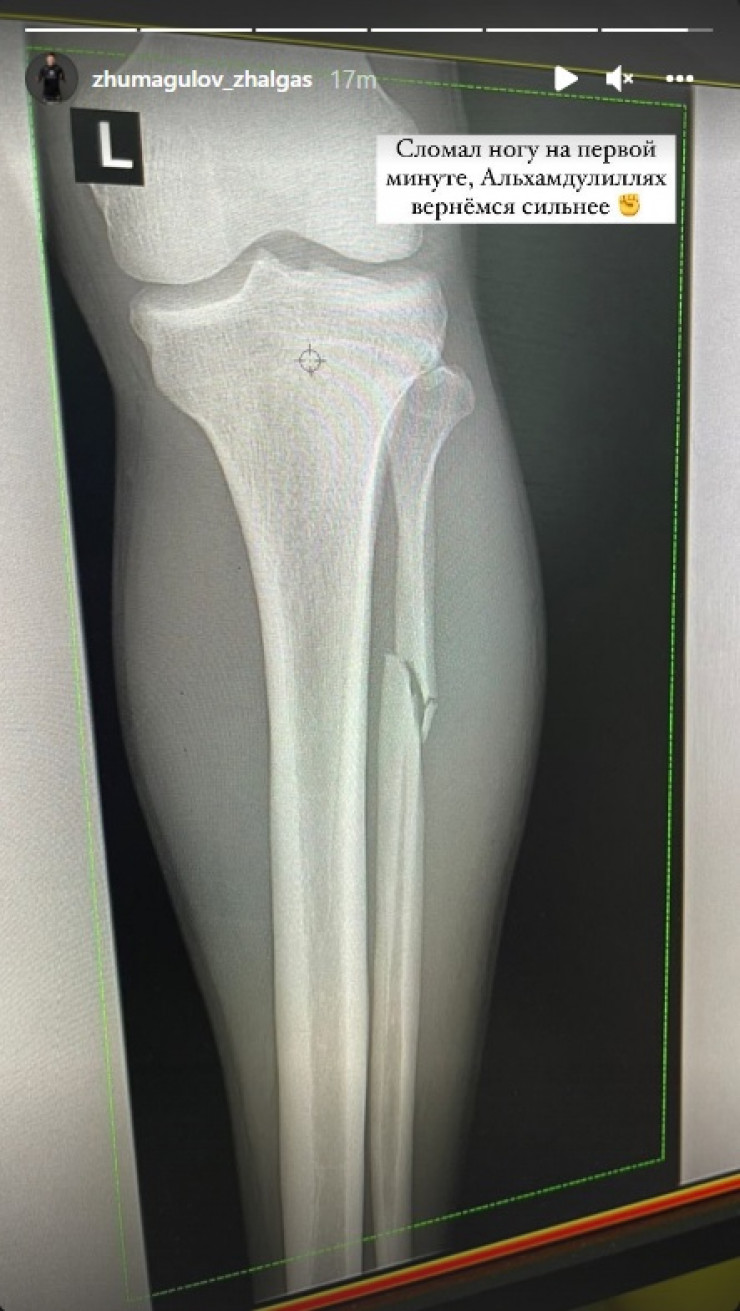

«Shaıqastyń birinshi mınýtynda aıaǵymdy syndyryp aldym. Segiz buryshqa munan da kúshti bolyp oralamyn», dep jazdy qazaq oǵlany óziniń ınstagramdaǵy akkaýntynda.

Qazaqstandyq aralas jekpe-jek sheberi Jalǵas Jumaǵulov sońǵy shaıqasynda angololyq Manel Kapege qarsy oktagonǵa shyǵyp, birinshi raýndta jeńilis tapqan bolatyn, dep habarlaıdy Egemen.kz.

Jekpe-jekten keıin qazaq sportshysynyń jaraqat alǵany belgili boldy.